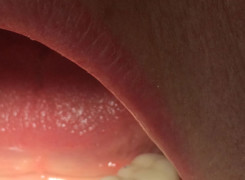

Pan Kamil zgłosił się do gabinetu po wypadku rowerowym w wyniku którego wybił ząb – lewą górną jedynkę. W takiej sytuacji została podjęta decyzja o implantacji natychmiastowej oraz zapatrzeniu pacjenta na czas integracji wszczepu w uzupełnienie tymczasowe.

Poniżej przebieg odbudowy protetycznej.